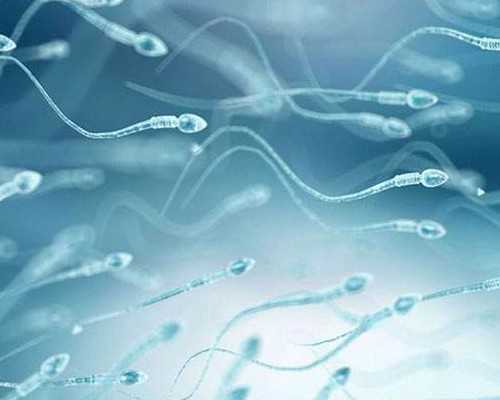

福州試管嬰兒洗精技術(shù)有哪些好處?聊聊常用的精子洗滌方法

高齡夫妻備孕成功一半靠男性:提升精子質(zhì)量的關(guān)鍵時(shí)期與營(yíng)養(yǎng)補(bǔ)充方案